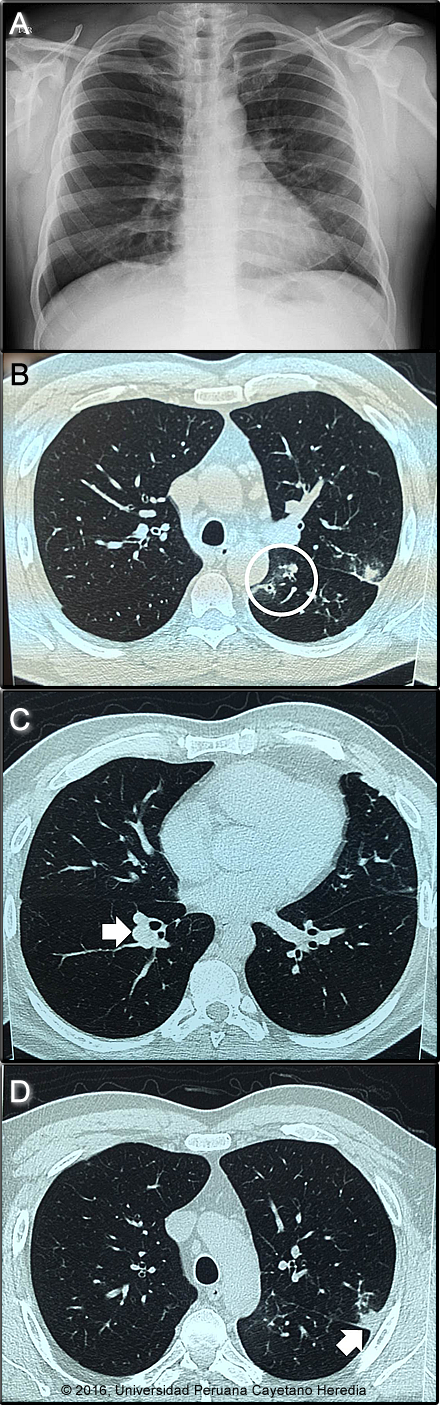

Epidemiology: Born and had lived for 25 years in Chilete, on the Jequetepeque River in Cajamarca in Northern Peru. A schoolteacher, he currently lives in San Pablo with his wife and two children but returns to his hometown every weekend and drinks heavily. Denies tobacco or recreational drug use. No known TB contacts. He travels frequently within the provinces of Cajamarca. Physical Examination: HR 74. RR 18. BP 110/70. Afebrile Healthy appearing and alert. HEENT: nasopharynx clear, no cervical adenopathy. Chest: Clear breath sounds to auscultation bilaterally. Cardiovascular: Regular rate and rhythm, S1/S2 normal, no murmurs. Abdomen: normal bowel sounds, soft, non-tender, non-distended. No hepatosplenomegaly. Skin and extremities: no rash, nodules, no edema. Laboratory Examination (on admission): WBC 6.18 (0 bands 50 neutrophils, 10 eosinophils, 3 monos, 37 lymphs). Hb 14.8 g/dL, Hct 44%. Platelets 194 000. Glucose, urea, creatinine normal. Chest X-ray and Chest CT are shown (Images A-D). Bronchoscopy showed chronic inflammation of the bronchial tree with bronchiectasis and spontaneous, self-limited bleeding. Bronchial aspirate: gram stain showed few Gram positive cocci with 1-3 WBC per hpf and negative culture; negative AFB;: negative KOH and fungal culture. Pap was negative for malignant cells. Stool O&P: Blastocystis sp. 2-4/hpf, Endolimax nana 2-4/hpf.

Diagnosis: Pulmonary paragonimiasis due to P. mexicanus